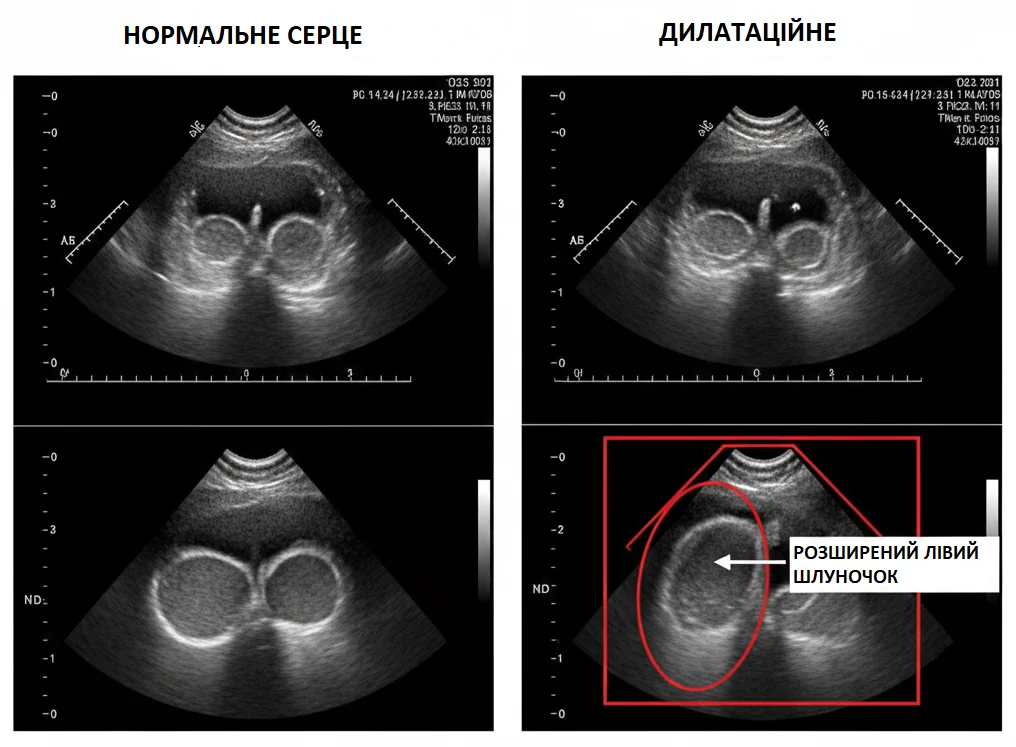

Проблема нутритивної дилатаційної кардіоміопатії стала предметом активних дискусій після публікації звітів fda щодо зв'язку цієї патології з беззерновими дієтами. Йдеться про корми з високим вмістом бобових культур: гороху, нуту та сочевиці, які можуть негативно впливати на метаболізм таурину в організмі собак. В АртВет ми аналізуємо ці ризики з точки зору кардіології: дефіцит специфічних амінокислот або вплив антинутрієнтів веде до поступового зниження скоротливої здатності міокарда та розширення камер серця.

Для пацієнтів, які тривалий час перебувають на раціонах з обмеженим набором інгредієнтів або беззернових сумішах, ми в АртВет рекомендуємо регулярний кардіоскринінг. Ехокардіографія дозволяє виявити ранні ознаки зміни структури серця ще до появи задишки чи непереносимості фізичних навантажень. Наша мета полягає у вчасному виявленні нутритивних дефіцитів та корекції дієти, що в багатьох випадках дозволяє зупинити прогресування хвороби або навіть досягти часткової регресії структурних змін серцевого м'яза.